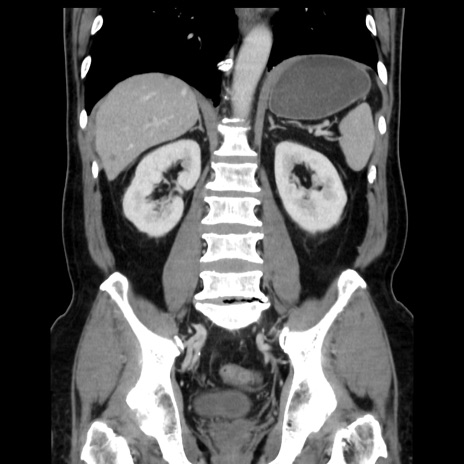

症例16(冠状断像)

【症例】 70歳代男性

【主訴】 腹痛、嘔吐

【現病歴】 約1ヶ月前より間欠的に腹痛と嘔吐あり、当院消化器内科を受診したところCTで多発する肝臓のLDAを指摘され、精査中であった。以降は消化器症状は安定していたが、2日前より嘔気と腹痛があり、同日より排便・排ガスが消失した。改善認めず、 本日、救急外来を受診した。

【既往歴】 大腸ポリープ切除後。

【身体所見】意識清明・会話良好、BT 36.3℃、BP 127/80mmHg、 P 80bpm、腹部:膨満あり、平坦・軟、上腹部正中および下腹部正中に圧痛あり、反跳痛なし、筋性防御なし。

【データ】WBC 7200、CRP 0.77